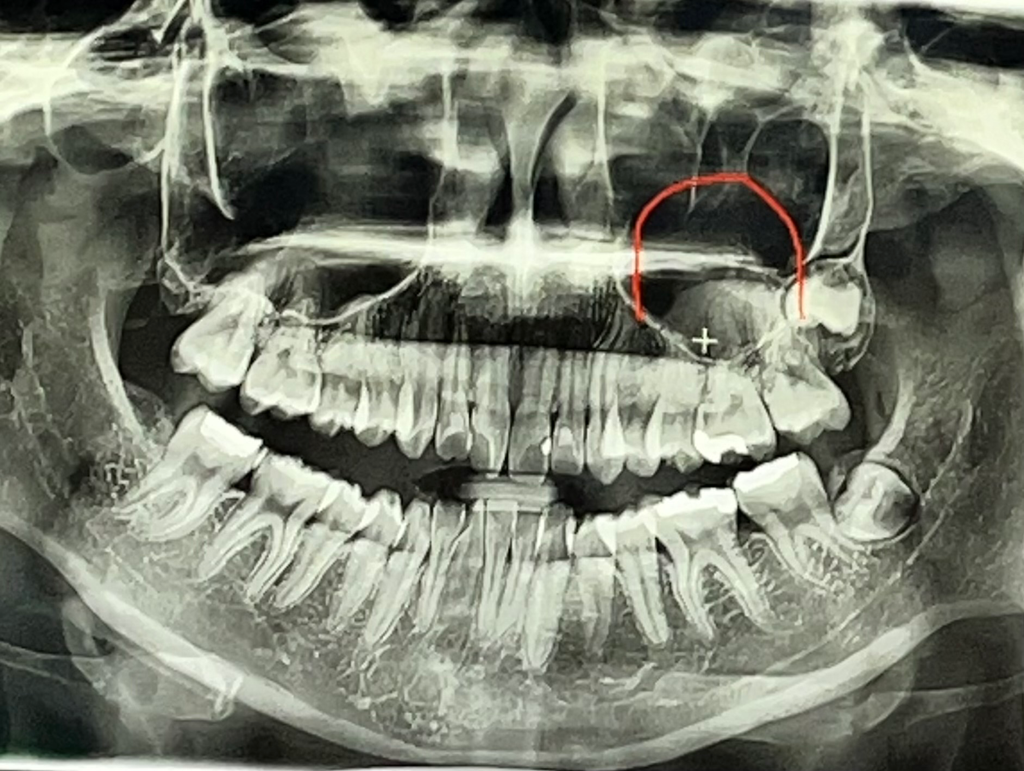

제 엑스레이 사진인데 사랑니가 두개밖에 없어요.. 아직 안난건가요? 아니면 원래 없는건가요 원래 한쪽만 있는사람도 있나요??

• 1번 째 사진

사랑니(Weisdom teeth)가 두 개밖에 없거나, 아직 나지 않은 경우가 있을 수 있습니다. 사람들 간에 사랑니의 개수와 성장 패턴은 다를 수 있습니다. 일반적으로 대부분의 사람들은 하나씩 총 네 개의 사랑니를 가지고 있지만, 몇몇 사람들은 사랑니가 모두 네 개가 나지 않는 경우도 있습니다.

사랑니가 아직 나지 않은 경우, 이것은 일반적인 현상입니다. 사랑니는 보통 17세에서 25세 사이에 성장하며, 때로는 더 늦게 나타날 수도 있습니다. 또한 일부 사람들은 사랑니가 나오지 않거나 나와도 적절한 위치에 있지 않아 치과에서 제거해야 할 수도 있습니다.

• 사랑니는 나게 되면 네 곳에 다 납니다. 아직 다른 두 군데는 안 난 것일 가능성이 높습니다. 시간이 경과하면서 서서히 새롭게 안 난 부위에 사랑니가 나게 될 것입니다.